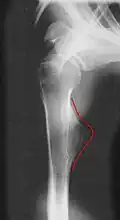

- Röntgenbilder

-

Kartilaginäre Exostose am Schienbein